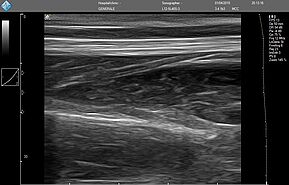

Ультразвуковой сканер MicrUs Pro - это идеальное портативное решение для проведения ультразвуковой диагностики в «полевых» условиях, сельской местности, для семейной и военной медицины (ультразвуковое исследование по протоколу FAST* – Focused Assessment with Sonography for Trauma). Особенности этой модели:

- Современные технологии улучшения визуализации,

- Подключение к ноутбуку / планшету Windows до 23 "с высоким разрешением, или к планшету / смартфону Android,

- Компактный, легкий, пилезахисний безвентиляторный дизайн аппарата, полностью размещен в рукоятке УЗИ датчика,

- Импульсно-волновой Допплер (PWD),

- Все возможные интерфейсы для передачи изображений, кинопетель для телемедицины.